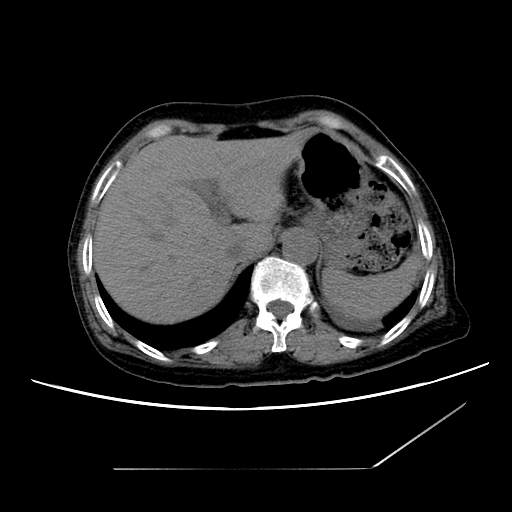

标题: CT25393:病人45岁,咳嗽,吐黄痰带血丝,发热,胸闷月余 [打印本页]

标题: CT25393:病人45岁,咳嗽,吐黄痰带血丝,发热,胸闷月余

1、左肺中央型肺癌并双肺弥漫性转移   2、双肺部感染    3、肺大泡     4、左侧胸腔积液

双侧肺弥漫性病变,可见“空泡征”及“蜂窝征”,考虑肺泡癌可能性大,左侧胸腔积液,考虑胸膜受累可能!

考虑肺泡癌,建议排除感染。

考虑肺泡癌

1)不排除肺泡癌可能。2)左侧胸腔积液。